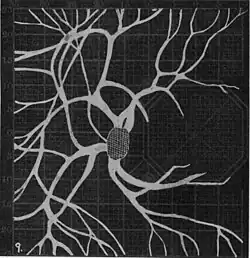

In the 1940s there were further developments. Evans reviewed the state of research in 1942.[6] In 1945, Welt designed a portable campimeter and linked the size of both the blind spot and the angioscotoma to retinal arterial pressure.[7] In the same year, Weekers and Humblet published detailed tracings that overlaid vessel photographs onto Bjerrum screen plots, firmly establishing the one‑to‑one correspondence between vascular anatomy and scotoma shape.[8]

20. Venous engorgement. 21. After pressure over internal 22. Same case, normal. 23. Scotoma after ligation of common carotid. 24. Edematous swelling of nerve and retina. 25, Normal blind spot of other eye. -